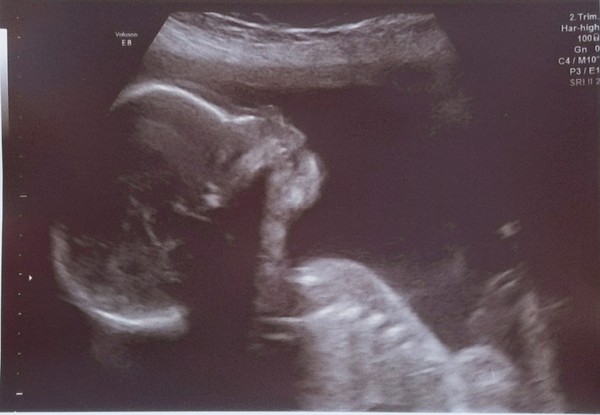

We got a gorgeous scan photo today at our high detail scan and confirmed boy :o

Lovely scan @BertieBotts xx

Awww, lovely scan @BertieBotts!

@BertieBotts That's a really gorgeous shot, bless 🥰 He'll be a beautiful boy xx